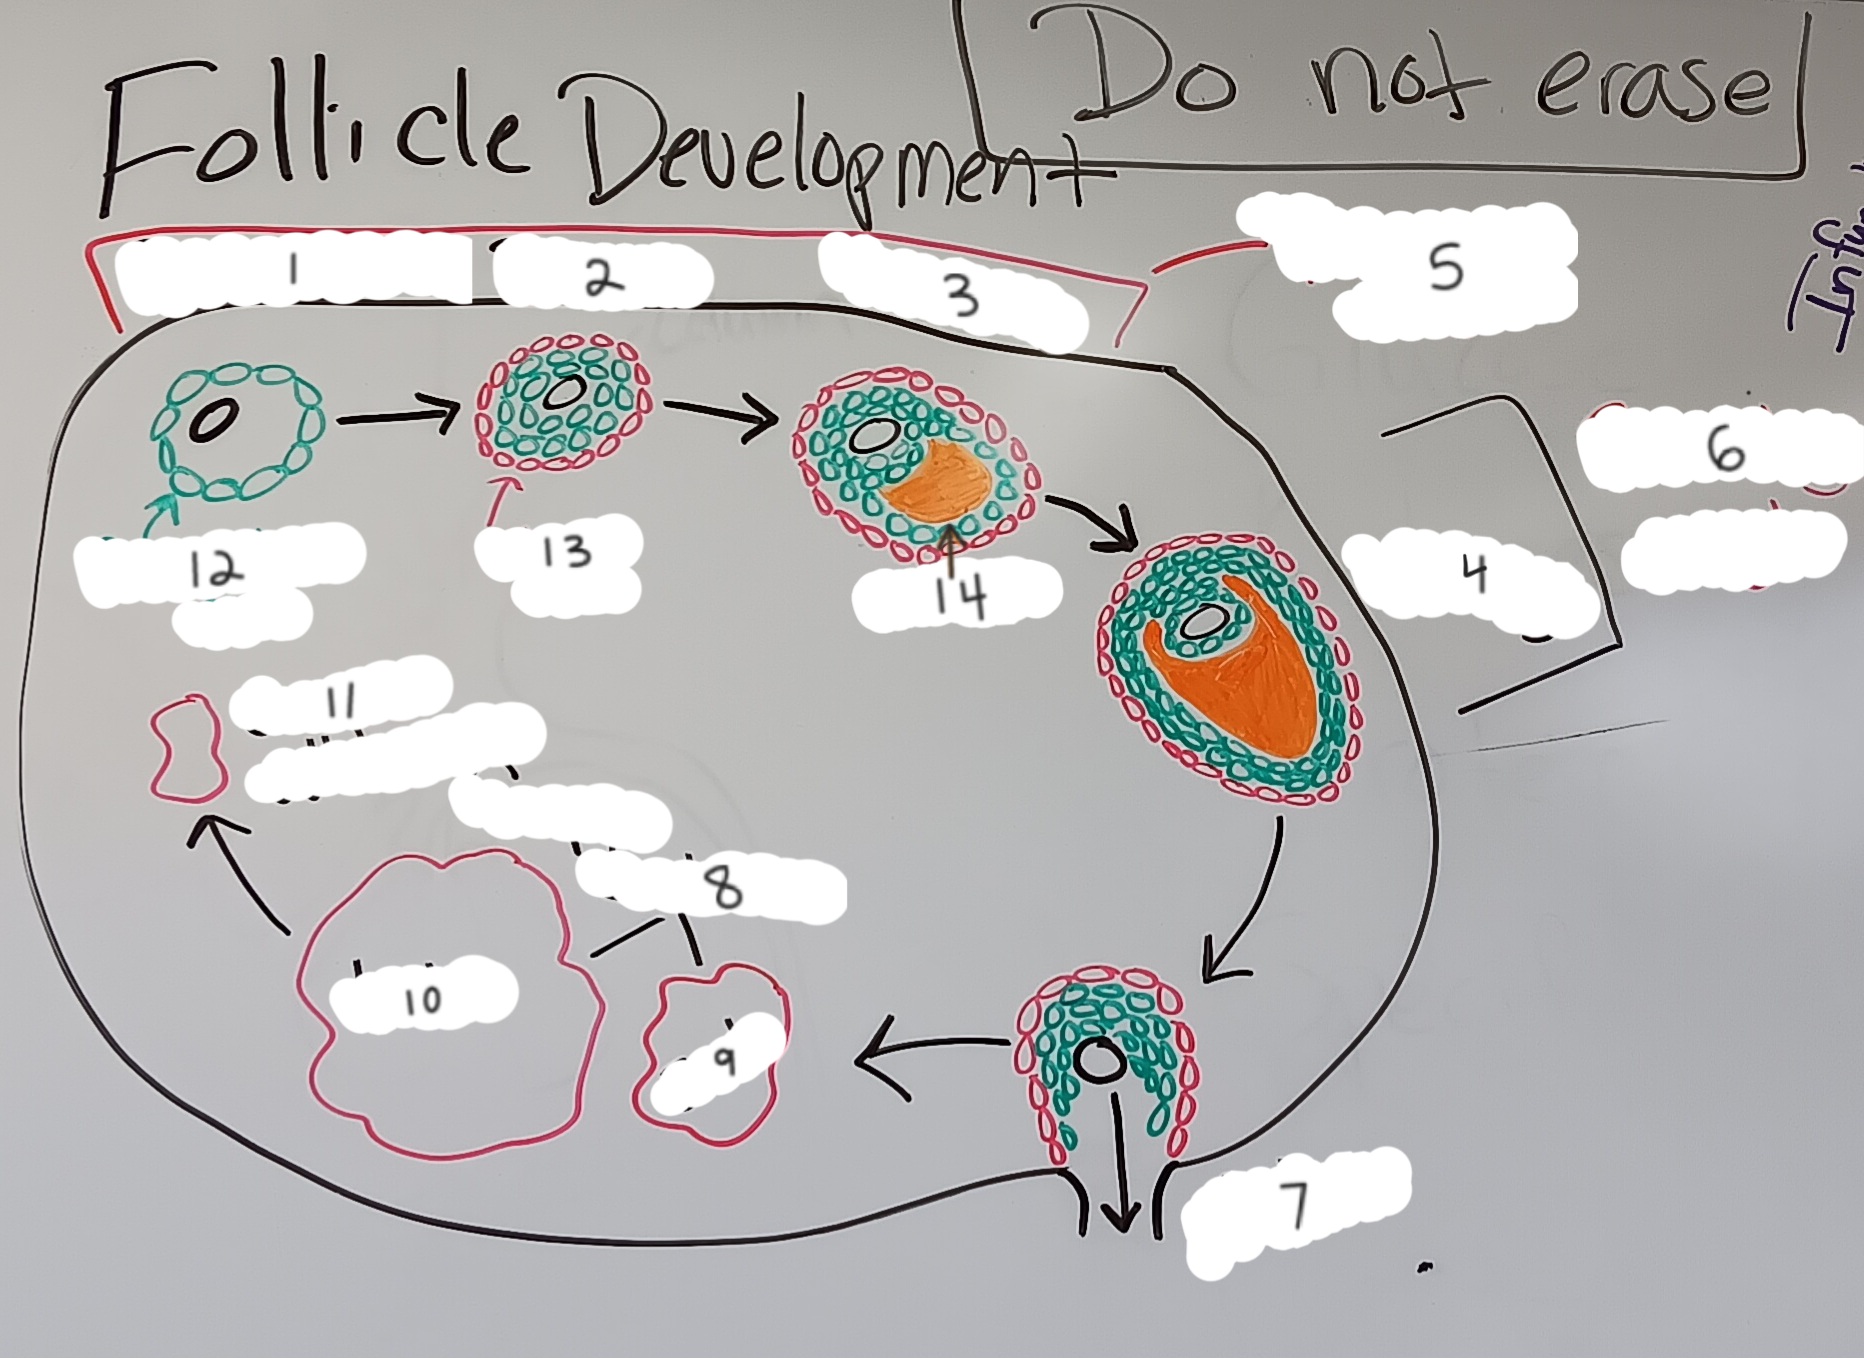

corpus luteum

8

early corpus luteum

9

late corpus luteum

10

corpus albicans

11

granulosa cells

12

theca cells

13

antrum

14